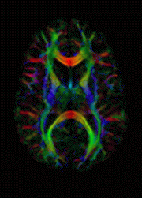

Diffusion MRI

DTI image